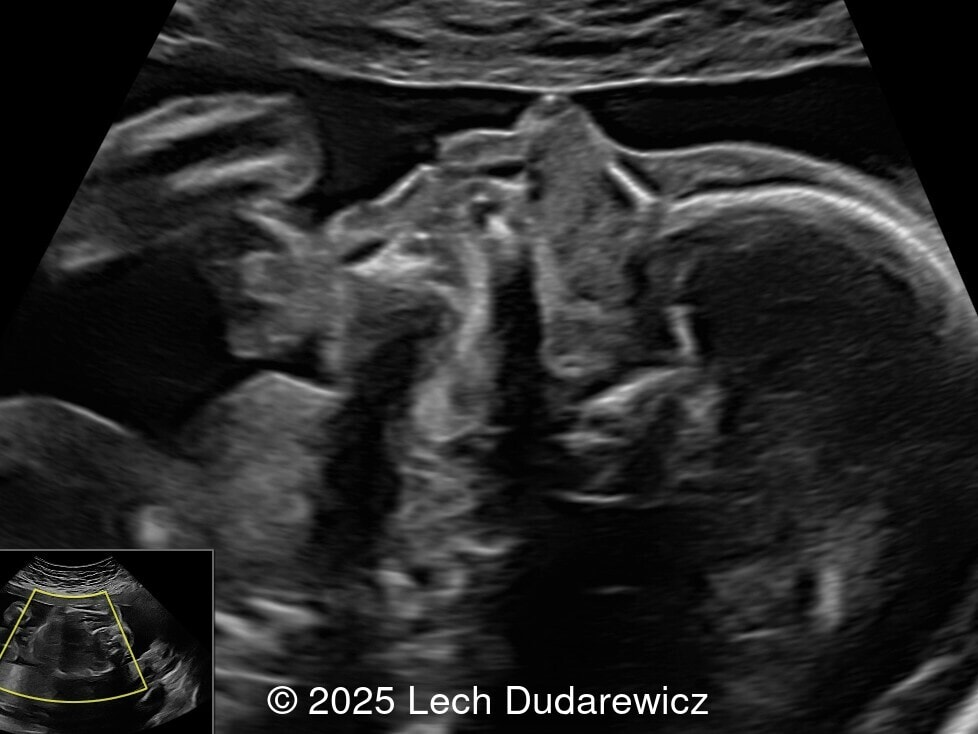

A 33-year-old nullipara with non-contributory medical history presented at 20 weeks, 6 days based on an early scan. Ultrasound revealed the following findings. There were no other apparent abnormalities. What is the most probable diagnosis?

Ultrasound images demonstrated a symmetrically enlarged thyroid gland that was isoechoic to slightly hyperechoic relative to the surrounding tissues. Color Doppler revealed peripheral hypervascularization of the thyroid, known as the “peripheral vascular rim sign”. No internal parenchymal hyperperfusion was noted. Amniotic fluid volume was within normal limits and no structural anomalies were observed in the remainder of the scan.

Prenatal ultrasound is the preferred method of screening for head and neck masses. The first ultrasound diagnosis of a fetal goiter was made by Weiner et al. in 1980 [11], and since then several cases have been published, mostly isolated or small series [12,13]. Ultrasound can accurately assess the size, location, internal blood supply, and growth of the fetal goiter, as well as evaluating its effects on neighboring structures and amniotic fluid volume. Key sonographic findings include a homogeneous, echogenic, symmetric mass in the anterior portion of the fetal neck corresponding to the thyroid enlargement (measurements above the 95th percentile for gestational age), polyhydramnios (not always present), and abnormal fetal neck contour [1]. On color Doppler evaluation, peripheral hyperperfusion ("peripheral vascular rim sign") supports the diagnosis of hypothyroidism with a hypertrophic but inactive thyroid gland. Diffuse parenchymal hyperperfusion (“thyroid inferno”), due to an overactive thyroid gland, is expected in hyperthyroidism [14,15]. Three-dimensional ultrasound may facilitate the parent’s understanding of the fetal goiter [16] and magnetic resonance imaging (MRI) can be useful for evaluating the compression and patency of the trachea and esophagus [17].